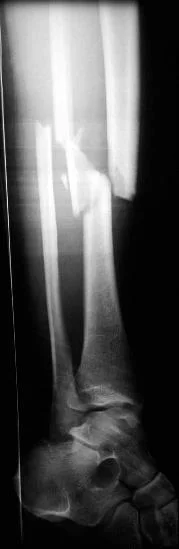

- Fall from height on feet

- fractured calcaneus and lumbar spine

- Plain x-ray: (law of two’s)

- Plain x-ray: (law of two s)

- Two views: AP and Lateral

- Two joints: joint above and joint below

- Two injuries

- e.g. calcaneal fractures & spine injuries